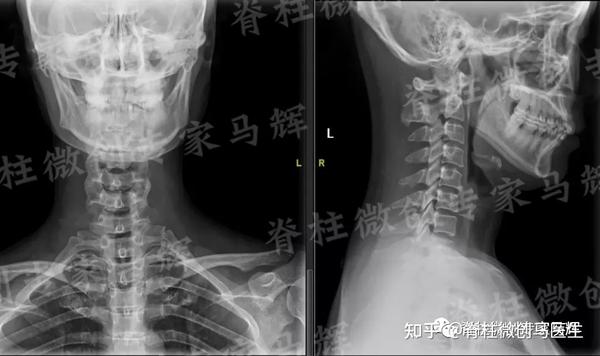

Feb 26, 21 · 颈椎压迫神经的症状分为压迫神经根和颈髓两方面。 颈椎压迫神经根的症状有:1、疼痛,一般表现为自颈部向上肢的放射性疼痛;2、感觉障碍,受到压迫神经根在上肢的支配区出现麻木、痛觉过敏、感觉减退等症状;3、肌力改变,早期肌张力亢进,晚期肌张力减弱,肌肉出现萎缩。Nov 08, 11 · 颈椎病吃药只是缓解作用,要除根的话建议您还是接受正规的治疗,最好是保守治疗,您与眩晕的情况的话应该属于脊髓型的,最好不要再耽误了,我们是通过中医手法复位正骨后(正骨12周,每隔一天一次,30分钟每次)改变压迫神经的关节位置使其不再压迫Aug 23, 19 · 虽然说确实有压迫神经的可能,但依然只是猜测,目前已有的检查并不能确诊! 患者需要做一个颈部核磁,这个检查是很有必要的,不光是确诊,更是未来治疗的依据,我们需要通过核磁更为详细的了解患者病情,病变位置、神经压迫程度进行综合考虑,对于此类患者来说,治疗方式有很多,作